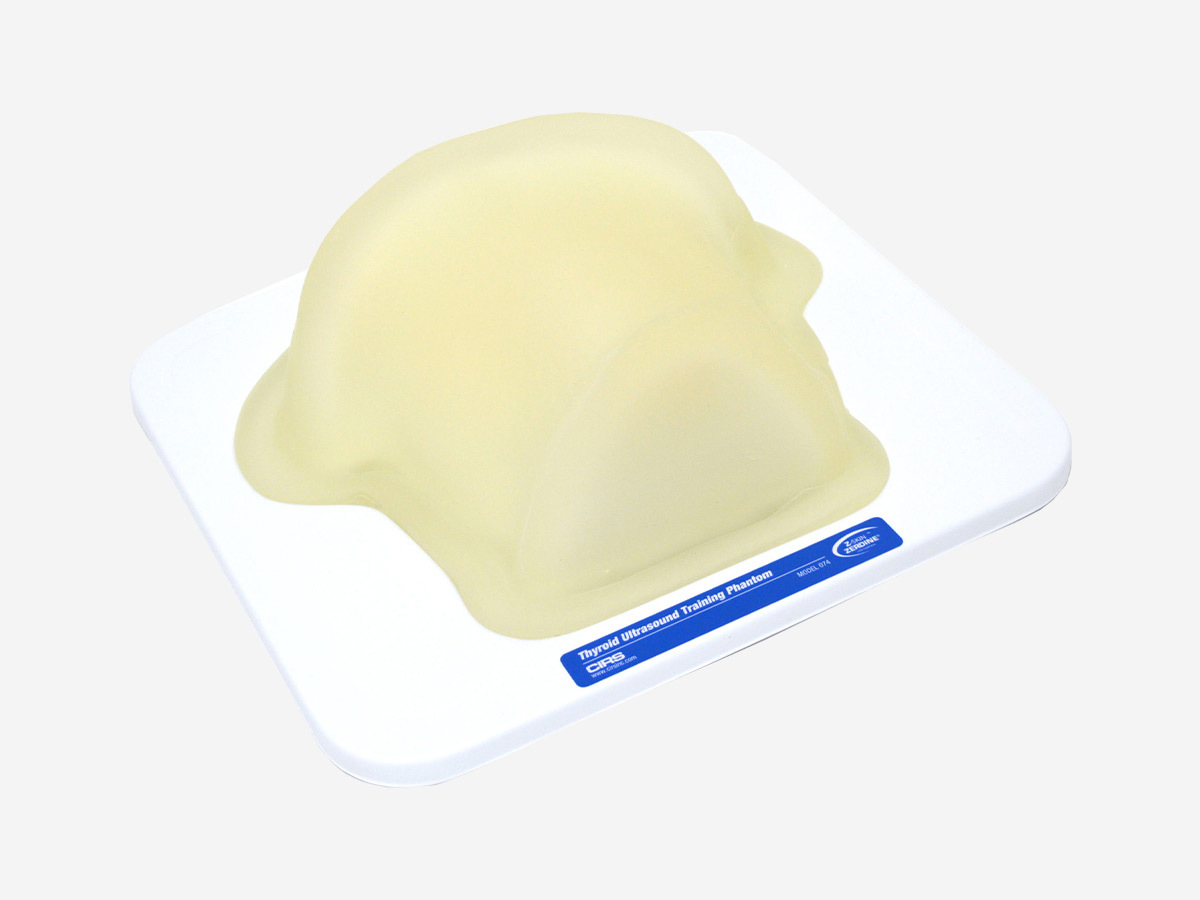

Thyroid Ultrasound Training Phantom

- Train how to perform thyroid ultrasound examination

- Practice ultrasound-guided biopsy procedures

- Identify various types of thyroid nodules and training on proper thyroid scanning techniques

- Thyroid Ultrasound Training Phantom Datasheet

Dimensions |

31 cm x 32.5 cm (12.2" x 12.8") |

Weight |

9.4 lbs (3.5 kg) |

Volume |

35cc (nominal) |

Materials |

Outside: Z-SkinTM elastomer |

Internal Structure |